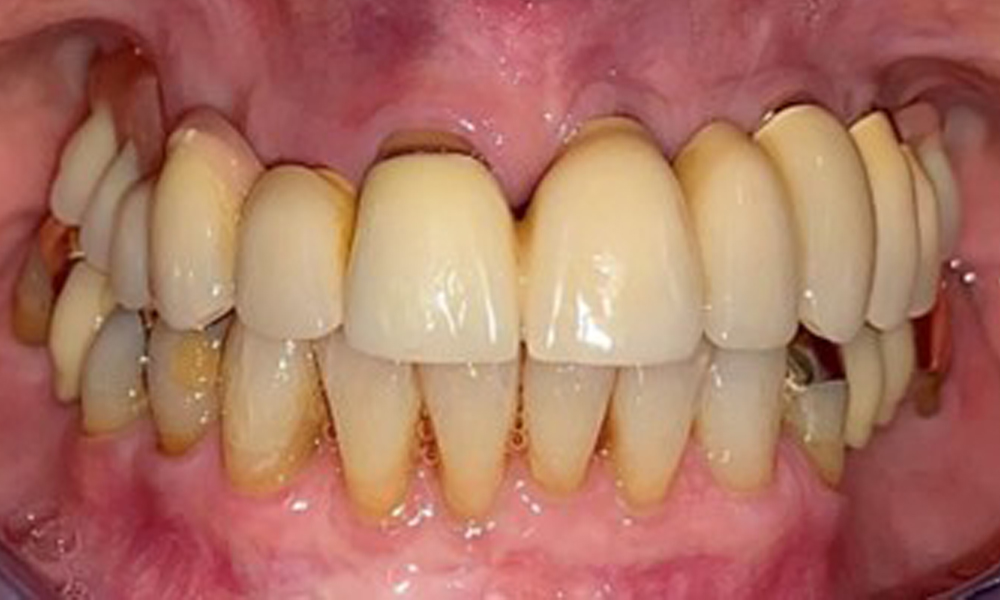

Фронтален изглед с поставена горночелюстна протеза.

Фиг. 1: Фронтален изглед с поставена горночелюстна протеза.